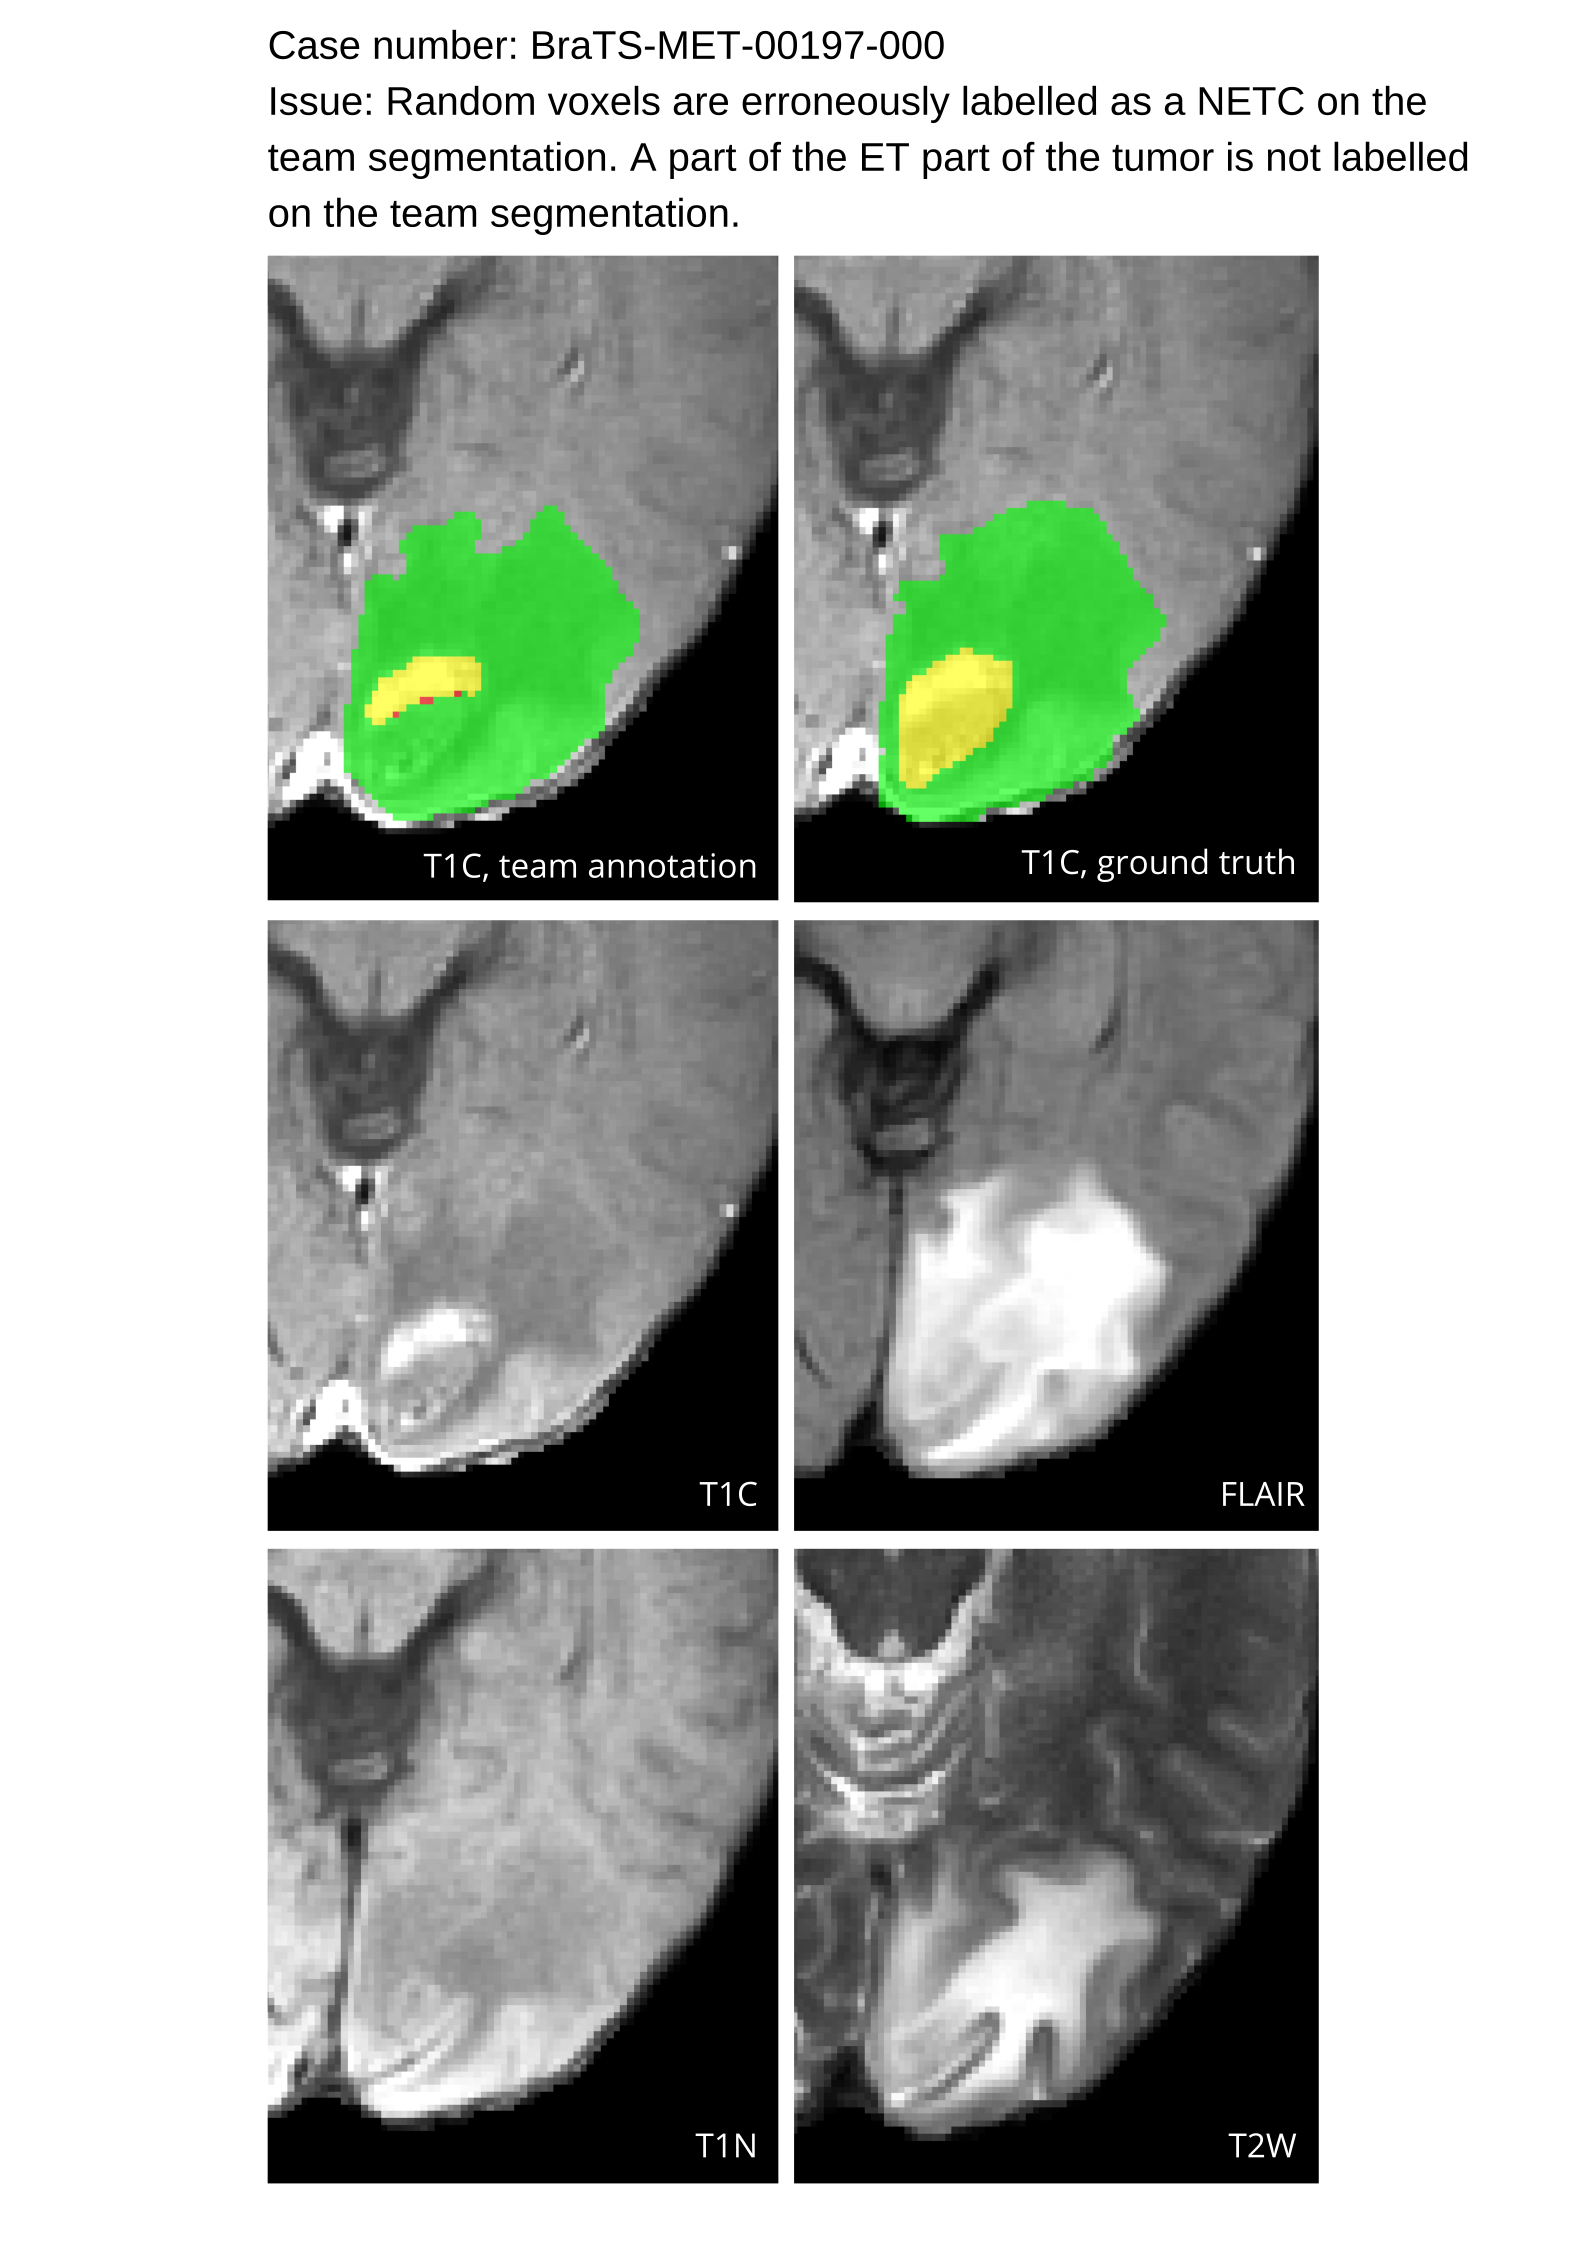

Approvers reviewed the volunteer annotations and either approved the case or returned it to students for re-annotation. Additionally, a QC process was implemented, which included removing all random voxels and any voxels outside the brain mask, ensuring all images had the same parameters (space, orientation, and origin) as the SRI24 atlas, and verifying the presence of all segmentations and segmentation masks are in the folder with original NIfTI images.

Acknowledging the variability in lesion significance arising due to human error, a volumetric threshold of 2 voxels (2 mm3superscriptmm3\text{mm}^{3}mm start_POSTSUPERSCRIPT 3 end_POSTSUPERSCRIPT) was established by an expert panel of clinical radiologists, below which the models’ performance on deemed ”small/false” lesions is not considered in the evaluation. This approach was primarily adopted to ensure that participants were not unfairly penalized for stray voxels in the GT labels, which may result from human error, or for small lesions unrelated to the pathology central to the challenge. The expert panel of clinical radiologists also determined the dilation factor, which was uniformly applied for combining lesions in the GT masks. A dilation factor of 1 voxel in 3D space was chosen because BMs can be small, and it is important to avoid combining these small BMs.

Table 4 provides the relative ranking for each team. Team NVAUTO ranked first in the challenge, with an average rank across subjects of 7.9 and a PatientWise mean of 0.38. Team SY placed second with a PatientWise mean of 0.41 across all patients. The supplementary material depicts the pitfall cases with figures illustrating the false positives or missed lesions.